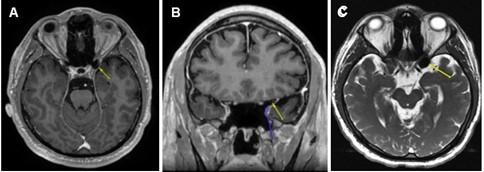

Based on the patient’s surgical history, ophthalmic exam, OCT, and 24-2 test results, brain and orbit MRI with and without contrast were ordered to identify lesions along the visual pathway, notably the optic nerve tract, chiasm, or occipital lobe. The MRI revealed no intra-orbital pathology and no abnormal enhancement of the optic nerve/chiasm/radiations or brain parenchyma. Of note, axial post-gadolinium T1-weighted MRI (Figure 1 A) demonstrated an area of hypointensity in the left ACP that measured 1.46 cm x 1.31 cm consistent with the presence of air-filled space involving about 50% of the left ACP. The coronal view of his gadolinium T1-weighted MRI (Figure 1B) clearly delineated the air-filled space with no obvious hematoma or traumatic optic nerve lesions noted. The axial T2-weighted FIESTA-C (modification of the basic FIESTA/True FISP sequence) MRI (Figure 1C) showed hypointensity in the left ACP. There was no discernible optic canal stenosis, change in optic nerve course, or optic nerve dehiscence or protrusion associated with the ACPP. The patient was referred to neurosurgery for further evaluation. His head and orbit CT scans revealed no bony fragment or hematoma affecting structures in the visual pathway. No surgical intervention was entertained, as the risks significantly outweighed any perceived benefit. At 6 months follow-up, the patient had no improvement of blurred vision in his left eye.

Figure 1.(A) Axial post-gadolinium T1-weighted MRI demonstrating the T1 hypointensity in the left anterior clinoid process (yellow arrow). (B) Coronal post gadolinium T1-weighted MRI with two arrows outlining a clearly delineated air-filled space without a hematoma or traumatic lesion to optic nerve just superior to the tip of blue arrow. (C) Axial T2-weighted FIESTA-C MRI showing T2 hypointensity in the left anterior clinoid process (yellow arrow).